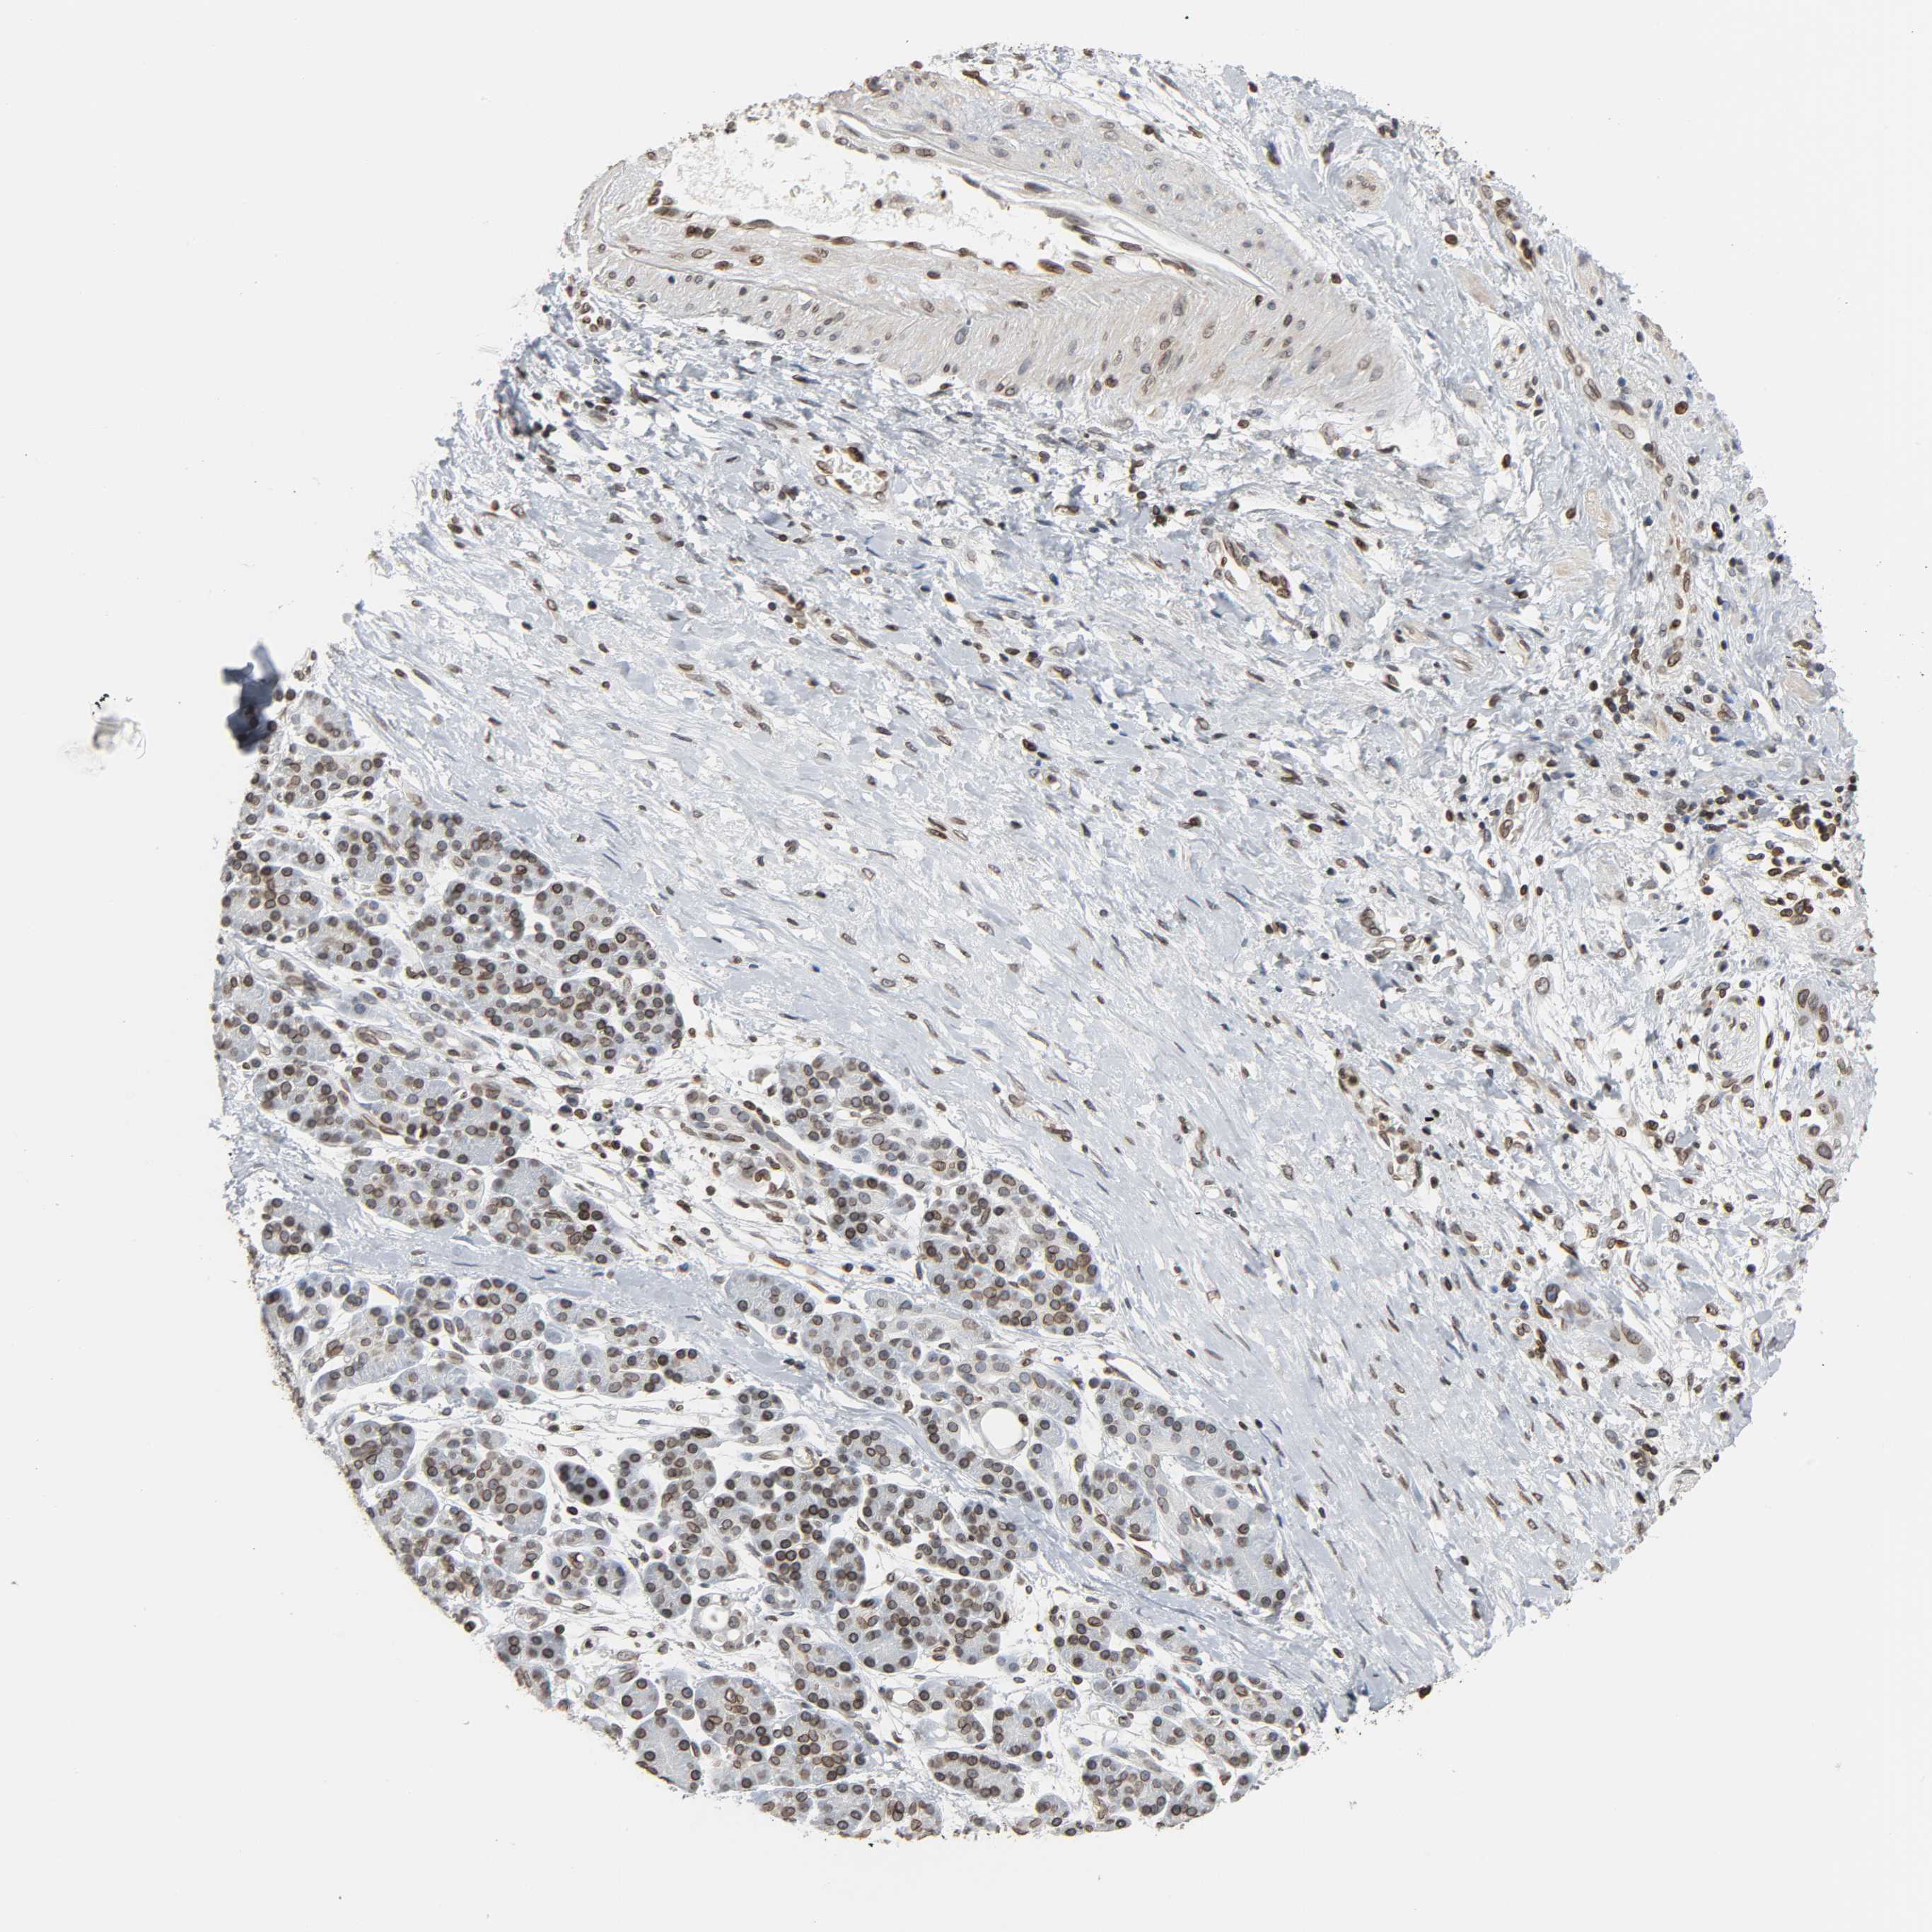

PANCREATIC CANCER - Protein expressioni

A mouse-over function shows sample information and annotation data. Click on an image to view it in a full screen mode. Samples can be filtered based on level of antibody staining by selecting one or several of the following categories: high, medium, low and not detected. The assay and annotation is described here.

Note that samples used for immunohistochemistry by the Human Protein Atlas do not correspond to samples in the TCGA dataset.

Antibody stainingi

Antibody staining in the annotated cell types in the current human tissue is reported as not detected, low, medium, or high, based on conventional immunohistochemistry profiling in selected tissues. This score is based on the combination of the staining intensity and fraction of stained cells.

Each image is clickable and will lead to virtual microscopy that enables deeper exploration of all samples and also displays staining intensity scores, fraction scores and subcellular localization as well as patient and tissue information for each sample.

Antibody HPA004246

Antibody CAB018641

Staining

High

Medium

Low

Not detected

Intensity

Strong

Moderate

Weak

Negative

Quantity

>75%

75%-25%

<25%

None

Location

Nuclear

Cytoplasmic/membranous

Cytoplasmic/membranous,nuclear

Adenocarcinoma, NOS

Adenocarcinoma, metastatic, NOS